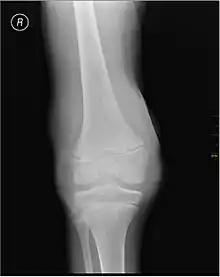

Muscle and joint haemorrhages – or haemarthrosis – are indicative of haemophilia,[7] while digestive tract and cerebral haemorrhages are also germane to other coagulation disorders. Though typically not life-threatening, joint bleeding is one of the most serious symptoms of haemophilia. Repeated bleeds into a joint capsule can cause permanent joint damage and disfigurement resulting in chronic arthritis and disability. Joint damage is not a result of blood in the capsule but rather the healing process. When blood in the joint is broken down by enzymes in the body, the bone in that area is also degraded, this exerts a lot of pain upon the person afflicted with the disease.